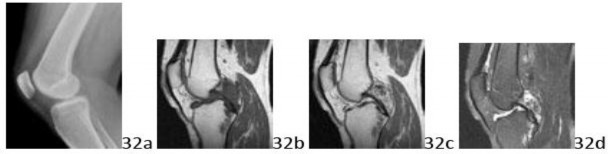

13. # 32a 32b 32c 32d A 58-year-old woman has left knee pain. She states the pain is modest, but there is some swelling and pain with increasing activity, and is alleviated with rest. She denies any history of trauma, and denies any known history of arthritis. Examination is remarkable only for some modest pain with full flexion. Figures 32a through 32d show the lateral radiograph, sagittal T1-, T1-gadolinium, and T2-weighted MRI scans respectively. Based on the history and the images, what is the most likely diagnosis?

DISCUSSION: The lateral radiograph is not particularly remarkable, except that it does not show any arthritic or erosive changes. There are no mineralized changes seen in the joint. The T1-weighted MRI scan shows low signal, lobular lesions that are in the posterior joint

and into the proximal tibia. These lesions show some minimal enhancement with gadolinium, and are somewhat bright ("wet") on the T2-weighted image. This lobular, invasive appearance in the posterior knee is most consistent with pigmented villonodular synovitis. The lack of mineral density in the joint and the invasive nature of the demonstrated lesion into the bone make synovial osteochondromatosis very unlikely. The images show no evidence of inflammatory, infectious, or arthritic changes. The Preferred Response to Question # 32 is 4.